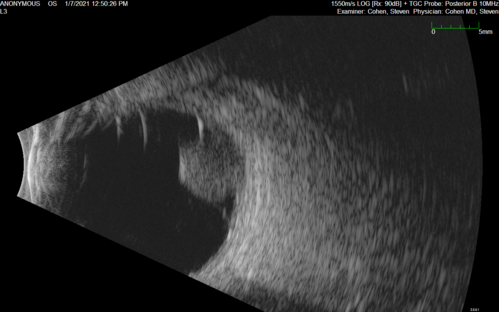

Class 2 choroidal melanoma

48 year old man with no visual complaints referred by optometrist.

Brachytherapy was done and biopsy showed a class 2 melanoma. 2 years later the patient developed liver metastases.